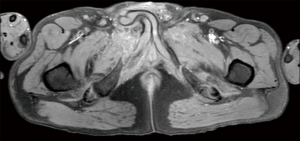

A 52-year-old man was referred to us from a rehabilitation hospital for a “hidden” penis 2 months after a blunt pelvic trauma following a motor vehicle accident. He has been managed conservatively with bed rest. Sitting and standing positions were not allowed by orthopedics. Enhanced computed tomography (CT) performed at the time of accident showed multi-fragmentary displaced fractures of the right ileum and ischiopubic bone (diastasis), and multi-fragment displaced fracture of the left ischiopubic branch (Figure 1A). A large hematoma in both obturator fossa and inguinal-scrotal regions was also present (Figure 1B). The penis was dislocated in the subcutaneous tissue surrounded by a moderate hematoma (Figure 1B). However, penile dislocation was not reported by the radiologist. After reabsorption of pelvic edema, the patient complained of dribbling micturition. Micturition took place by dripping urine from the opening of the prepubic skin where urine got trapped in the surrounding skin (Figure 2). He also complained of not having erections. Clinical examination revealed a retracted penile skin. The penis was not visible, neither palpable in the expected position (Figure 2). Bladder catheterization was not possible. His body mass index was 23.04 kg/m2. He underwent a lower abdomen magnetic resonance imaging that showed invaginated penis, which was located in the anterior pelvic wall, adjacent to the right inguinal canal (Figure 3).